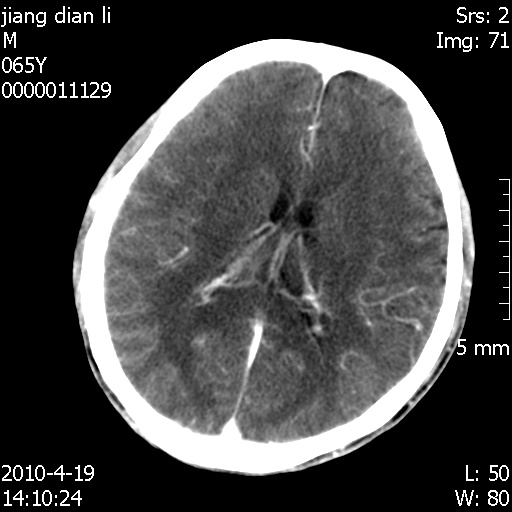

老年男性,突发左下肢无力1天,其余有价值的检查都没有。平扫ct值大约60hu,增强后ct值没什么改变,请大家讨论一下这个病例是什么?说明诊断理由。

左小脑、右大脑顶叶多发圆形高密度病灶,其周环状低密度影。考虑多发脑出血。隔期观察。

至于是出血还是微小钙化所致的高密度无法考证,三个都出血也不是一点都不可能,同一种组织学类型的肿瘤受到同一个外来的因素影响后会表现出相同的病理变化。说实在的,我本身支持转移瘤的,就是想不通为什么不强化?我认为单纯脑出血的边缘不会那么光滑,并且那也不是出血的常见部位,多发也不常见。

刚刚复习了转移瘤的不典型ct征象,有4条,分享给大家:

1、高密度灶:多为瘤内有较多沙粒体钙化所致,而不是出血,ct值可高达95hu;

2、无强化;

3、无水肿;

4、无占位效应。